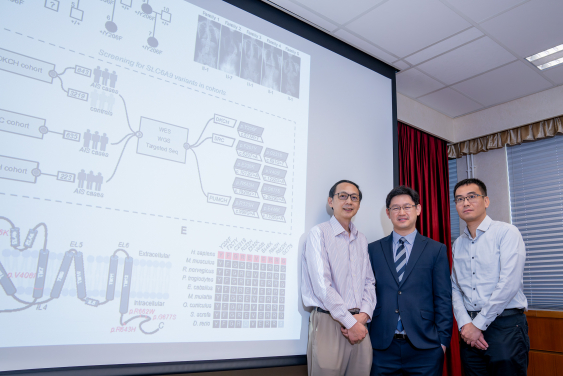

由香港大學李嘉誠醫學院(港大醫學院)臨床醫學學院矯形及創傷外科學系鍾培言教授和生物醫學學院宋又強博士,以及香港中文大學醫學院生物醫學學院高波博士領導的跨學科研究團隊,近日取得全球性突破,成功識別青少年原發性脊柱側彎(Adolescent Idiopathic Scoliosis,AIS)的主要成因。AIS是最常見的脊柱畸形,影響全球數以百萬青少年。團隊發現SLC6A9基因變異,令突觸神經傳送及中樞模式發生器 (Central Pattern Generators)失調,導致脊柱側彎;這項重大發現已在學術期刊 《臨床研究期刊》 (The Journal of Clinical Investigation)發表(按此瀏覽期刊文章)。

研究團隊為探究脊柱側彎的基因基礎及病理機制,對香港大學、德州Scottish Rite Hospital for Children及北京協和醫院合共1,701 名AIS患者和3,219名對照組人士進行基因檢測,鑑别出SLC6A9基因的罕見變異。該基因負責產生一種名為甘氨酸轉運蛋白1(GLYT1)的蛋白質,這些變異基因會導致神經訊號的傳遞和協調中斷。GLYT1負責調節中樞神經系統中的甘氨酸水平,有助正確傳導脊椎中的神經訊號。

團隊的研究揭示,SLC6A9變異基因會降低甘氨酸攝取,令甘氨酸濃度提高,產生異常的神經傳遞。為了進一步驗證他們的發現,團隊利用斑馬魚模型,透過基因編輯技術破壞斑馬魚的SLC6A9基因,模擬人類AIS患者的基因變化。研究結果顯示,突變斑馬魚表現出脊柱彎曲和神經活動不協調,與AIS患者的症狀相似。

團隊亦嘗試找出脊髓中的中樞模式發生器對AIS的作用。中樞模式發生器是負責自主產生步行或呼吸等節奏性行為的神經迴路,團隊發現GLYT1變異促使甘氨酸濃度過高,使中樞模式發生器無法正常運作而誘發AIS。

研究團隊由港大醫學院臨床醫學學院矯形及創傷外科學系主任兼臨床教授鍾培言教授、港大醫學院生物醫學學院首席講師宋又強博士及香港中文大學生物醫學學院副教授高波博士領導。第一作者包括港大醫學院臨床醫學學院矯形及創傷外科學系王小魯及港大醫學院生物醫學學院岳明。團隊成員包括港大醫學院臨床醫學學院矯形及創傷外科學系張頴恒醫生、王小軍、胡勇博士、陸瓞驥教授;港大醫學院生物醫學學院范彦輝、吳美澄、陳喆溢及陳振勝教授;港大醫學院臨床醫學學院兒童及青少年科學系涂文偉教授及王系偉博士;以及北京協和醫院、德州Scottish Rite Hospital for Children、中國科學院香港創新研究院再生醫學與健康創新中心及日本理化學研究所。